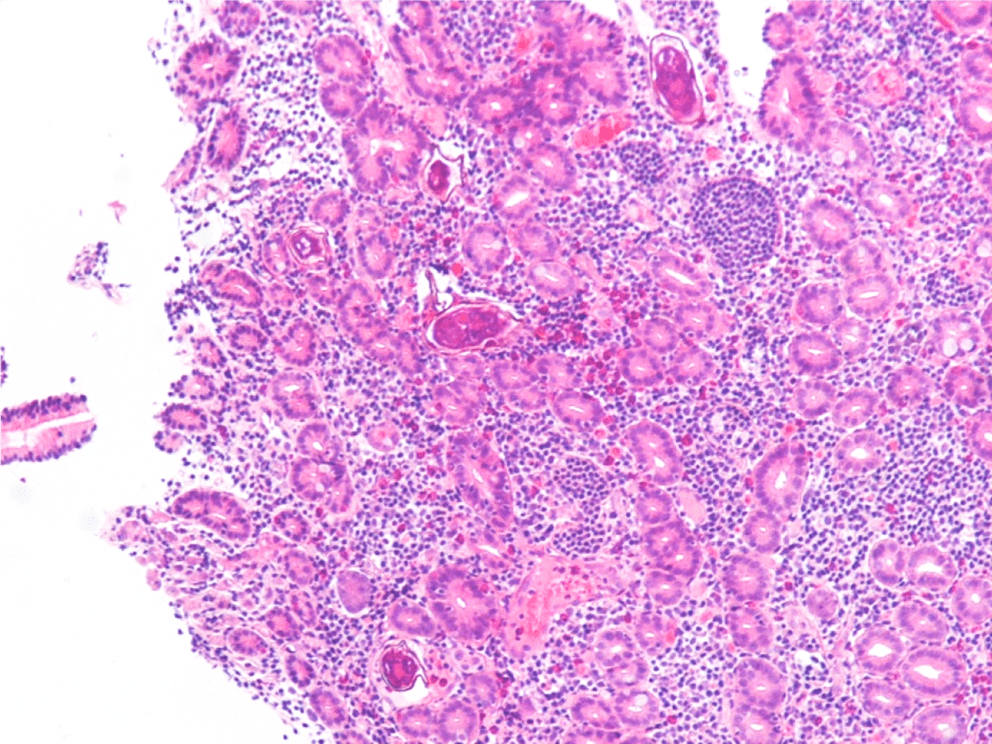

Malaria should be suspected when a patient presents with a febrile illness and a travel history within a malaria-endemic region. Diagnosis of P vivax can be made through microscopic examination of blood smears, immunochromatographic rapid diagnostic tests (RDTs) and nucleic acid detection through amplification techniques.1 Examination of a thick blood smear allows efficient screening for malaria parasites, while a thin blood smear allows for species identification since parasite morphology is more clearly visualized.2 Upon examination of thin blood smears, infections by P. vivax and P. ovale may appear indistinguishable as both species infect immature, enlarged erythrocytes (1.25-2x normal), can be visualized at any stage in peripheral blood (ring, trophozoite, schizont, and gametocyte) and because Schuffner’s dots are a common morphologic feature during most stages. Defining characteristics of P. vivax include the presence of a large, ameboid trophozoite cytoplasm, and fine Schuffner’s dots and schizonts with >12 merozoites. Of note, preparation with Giemsa stain over Wright stain is preferred for demonstration of Schuffner’s dots.2 Immunochromatographic RDTs detect parasite-specific antigens (e.g., Plasmodium lactate dehydrogenase, Plasmodium specific aldolase) in a finger-prick blood sample. These tests are commercially available and relatively simple to perform and interpret, making them a useful tool for resource-limited regions.1 Nucleic acid amplification-based tools (e.g., PCR, loop-mediated isothermal amplification) are not routinely used for clinical management of malaria but do have diagnostic advantages over light microscopy and RDTs.3 PCRs are highly sensitive, can detect mixed infections even at low parasite densities, and are useful for epidemiological studies such as drug resistance identification.1